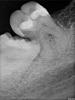

red_butler Опубликовано 25 июля, 2013 Поделиться Опубликовано 25 июля, 2013 (изменено) Удалить только восьмой, по данному снимку судить о положению мудрого зуба в горизонтальной плоскости нельзя Изменено 25 июля, 2013 пользователем red_butler 1 Ссылка на комментарий

yanina_ka Опубликовано 25 июля, 2013 Автор Поделиться Опубликовано 25 июля, 2013 Здравствуйте,есть ли у Вас панорамный снимок (ОПТГ)? к сожалению нет, врач сказал что на корне 7 зуба кариес, а это не лечится, так ли это?Спасибо! Ссылка на комментарий

yanina_ka Опубликовано 25 июля, 2013 Автор Поделиться Опубликовано 25 июля, 2013 Удалить только восьмой, по данному снимку судить о положению мудрого зуба в горизонтальной плоскости нельзя скажите а что можно сделать с 7? Врач сказал что на корне зуба кариес, а такое не лечится, так ли это? Спасибо! Ссылка на комментарий

red_butler Опубликовано 25 июля, 2013 Поделиться Опубликовано 25 июля, 2013 (изменено) скажите а что можно сделать с 7? Врач сказал что на корне зуба кариес, а такое не лечится, так ли это? Спасибо!Я ответить на ваш вопрос, только по представленному снимку не смогу, нужен осмотр или фотографии. Как вариант - покажитесь другому врачу Изменено 25 июля, 2013 пользователем red_butler Ссылка на комментарий